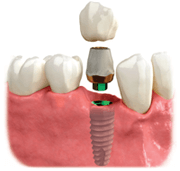

Individual Tooth Options

Individual missing teeth can be replaced by dental implants without altering your healthy adjacent teeth. Once dental implants are placed, posts (or abutments) are attached, providing support for your final crowns.

Dental Implants with a Crown

- Attractive smile

- Full chewing ability

- Preserve healthy teeth and jawbone

- Maintains bone